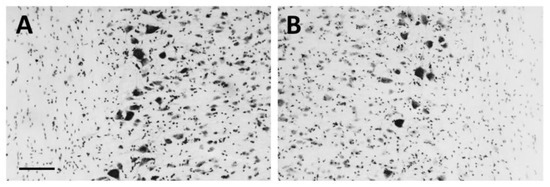

The analysis of cresyl violet stained (Figure 1A,B) SC sections belonging to the unilaterally lesioned LES-1wk group demonstrated an evident motoneuron loss within the lumbar SC ventral horn (L4–L5 segments) ipsilaterally to the injected muscles (Figure 1B), as compared to the contralateral side (Figure 1A). The observed motoneuron depletion (about 35%, as estimated by counting cresyl-violet stained motoneuron profiles in four horizontal sections per animal) was similar at one month after the lesion, as shown previously [21].

Figure 1.

Cresyl violet staining. The motoneuron depletion is evident in the cholera toxin-B saporin (CTB-Sap) injected side (B) compared to the intact side (A). Scale bar: 100 µm.